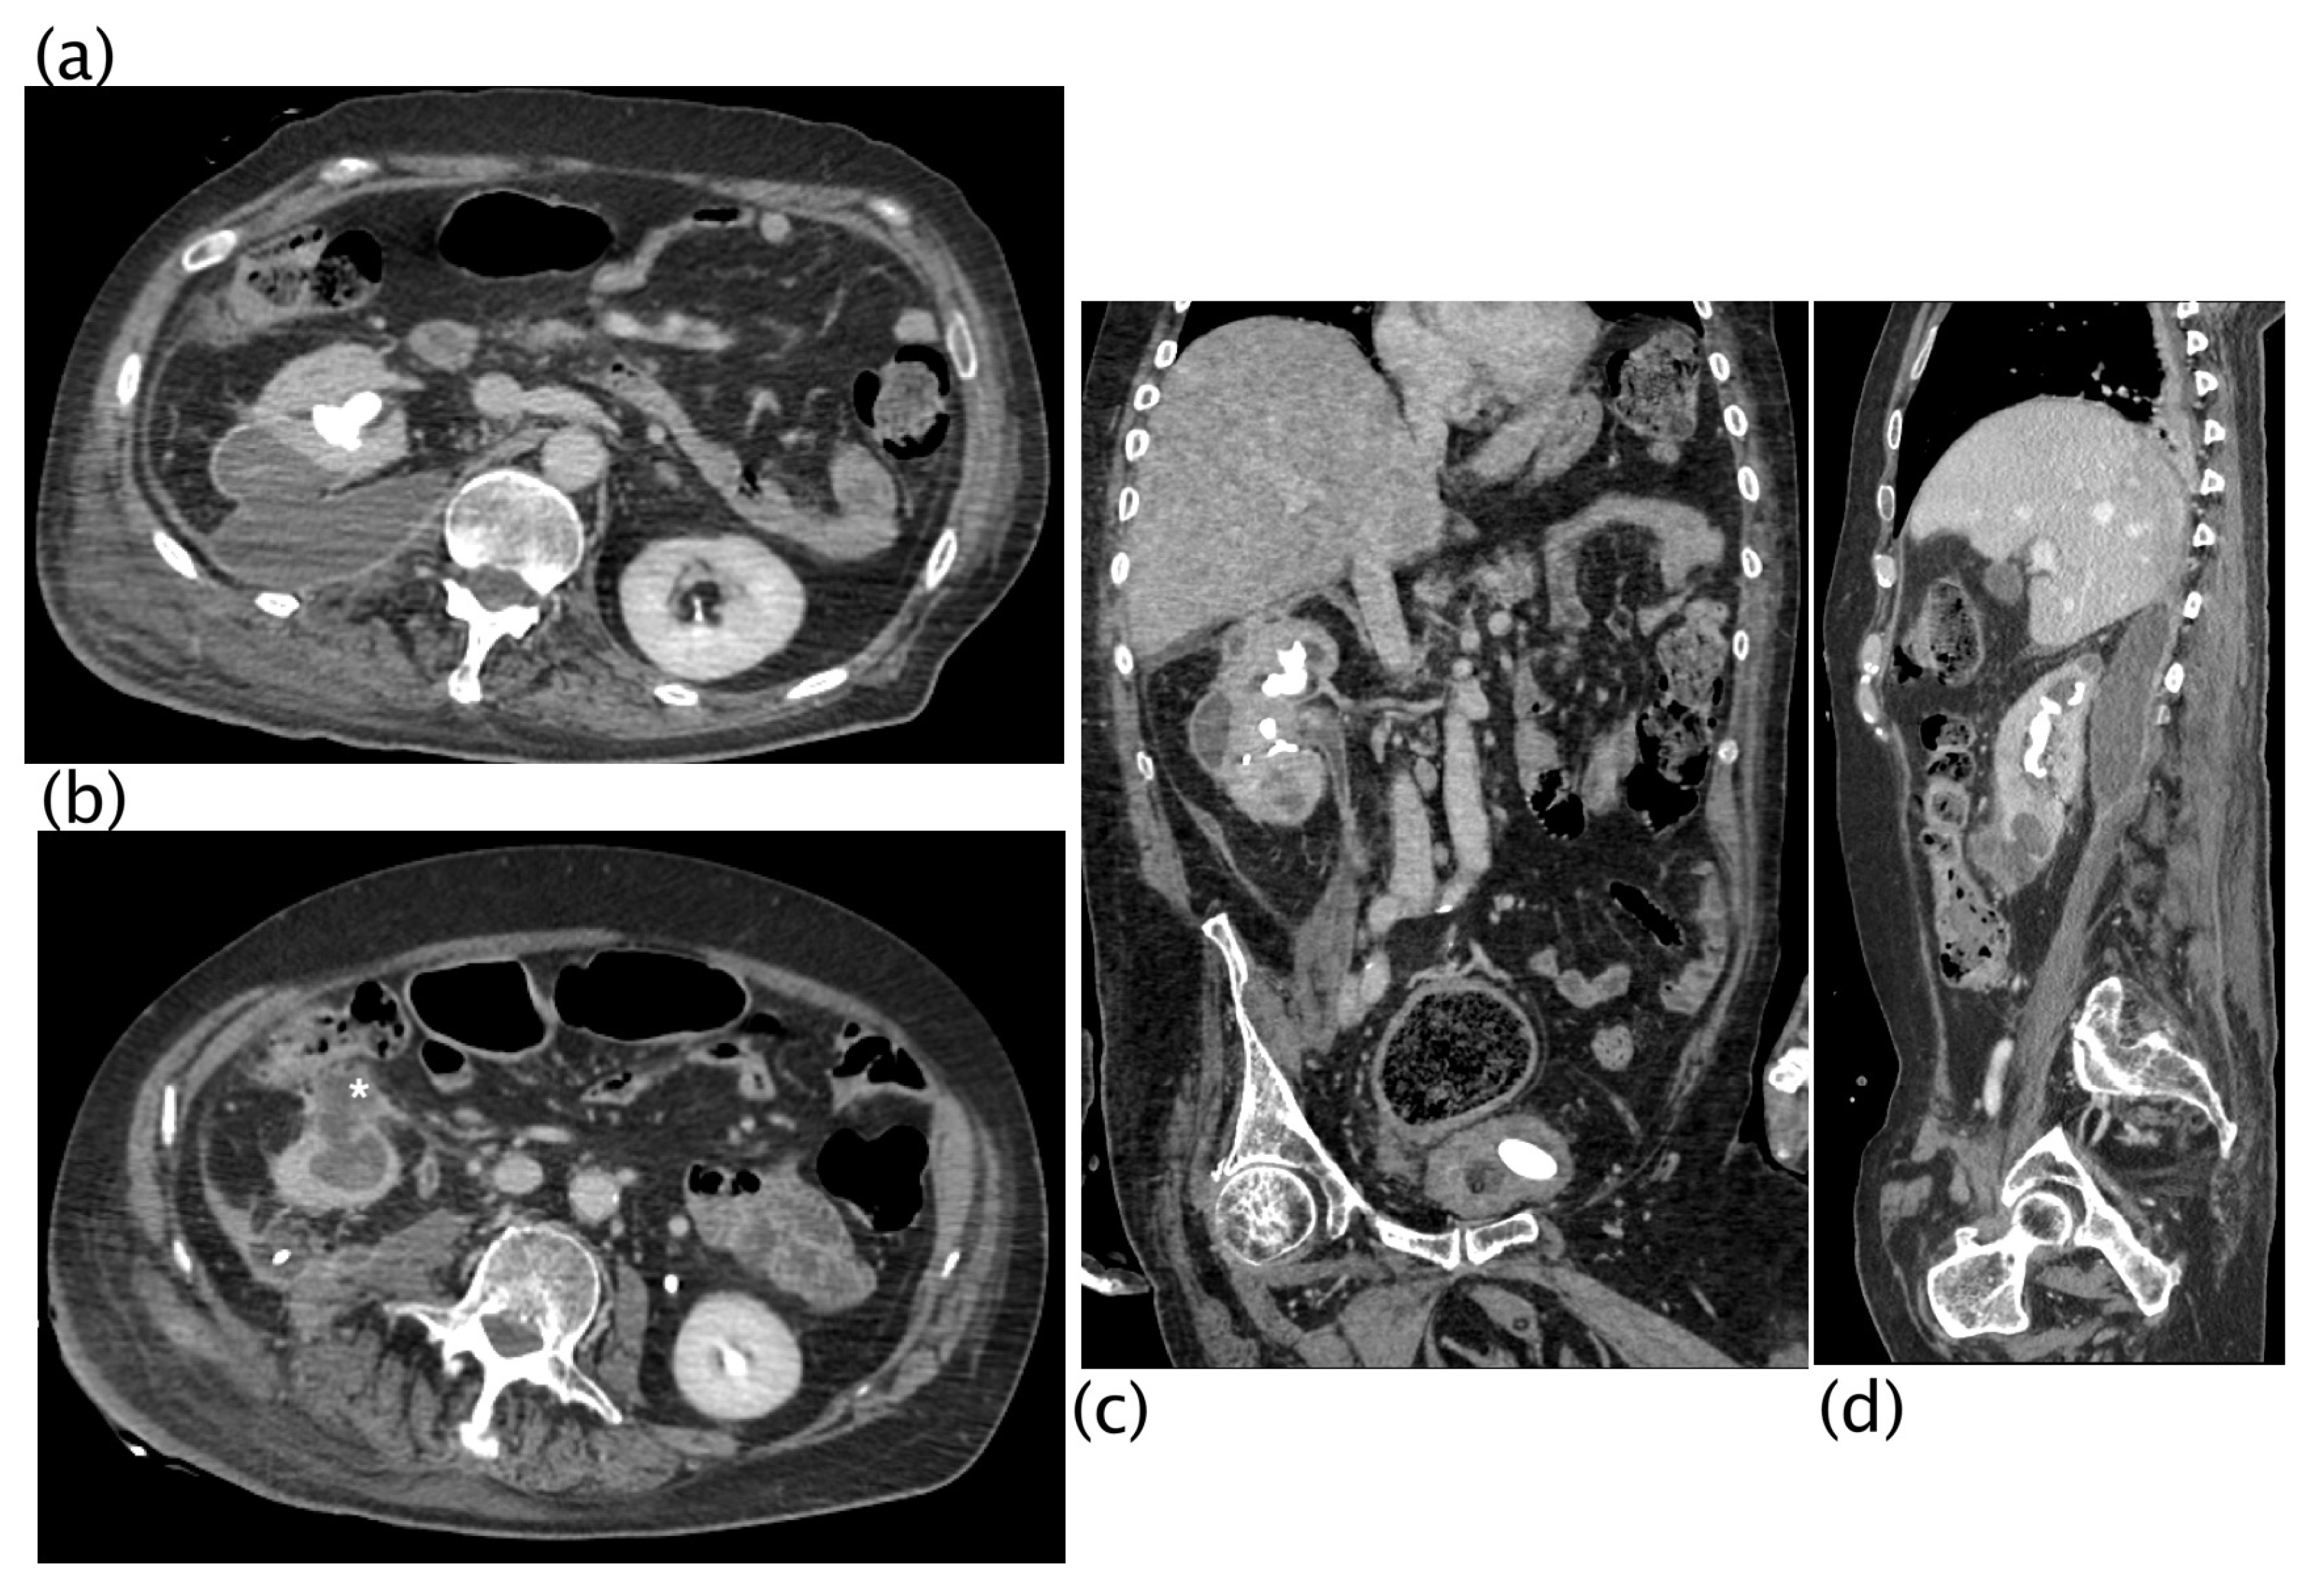

3. Results